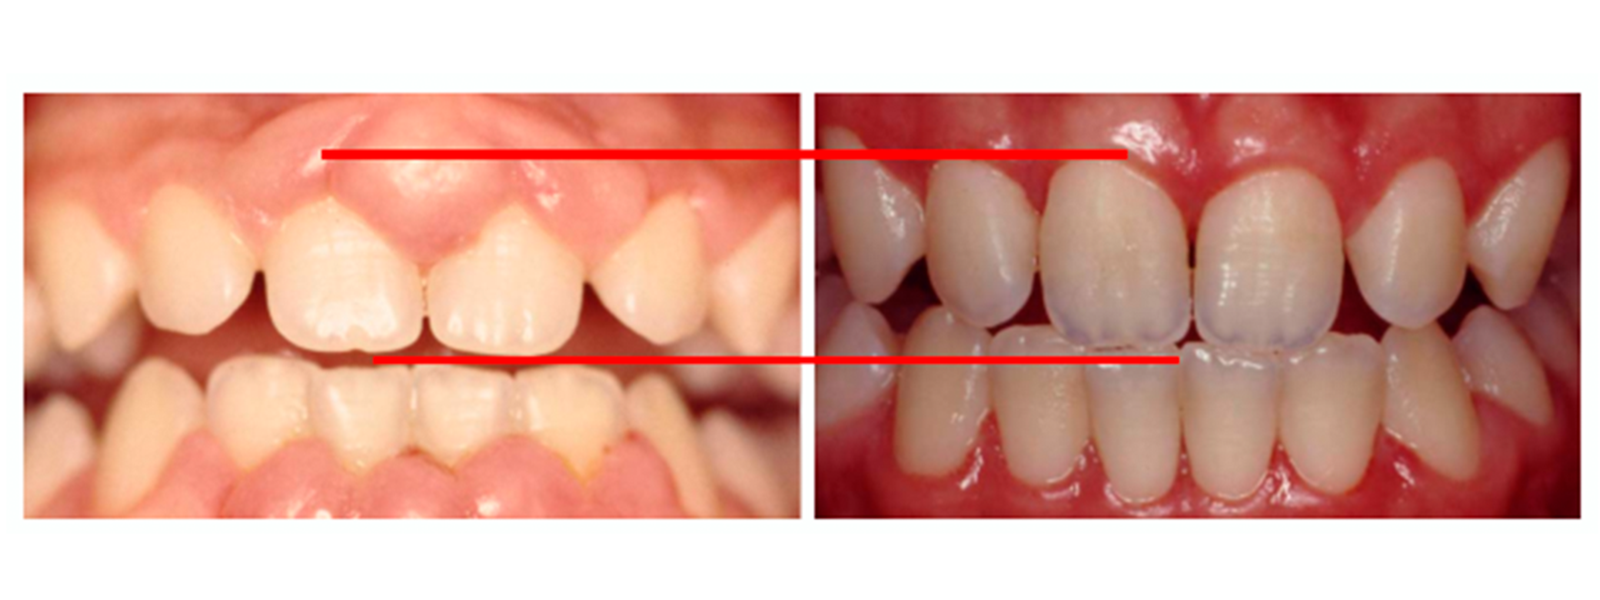

PAPILAS GINGIVALES

La papila gingival hace referencia al tejido periodontal que se sitúa entre diente y diente, a nivel del punto de contacto entre ambos y la base del hueso y tiene mucha importancia tanto a nivel estético como funcional porque impide que los alimentos se queden retenidos entre diente y diente y protege la creación de caries en esa zona del cuello dentario. Su tratamiento es posible hoy por medio de cirugía estética gingival regenerativa, mediante la implantación de un tejido estable y permanente en el tiempo y terapia con ácido hialurónico según el caso.